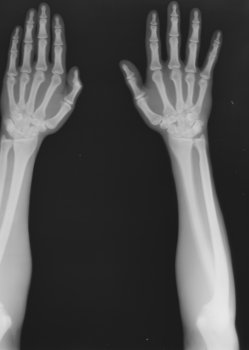

L. Zehnder, K. E. Kempke: Röntgenaufnahme, Negativ, 1896, Ausschnitt [Deutsches Museum, München]

Die Medizin hat den Körper fest im Blick. Es gibt kaum einen Bereich der Gesellschaft, der mehr Bilder produziert als die moderne Medizin. Diese reichen vom klassischen Röntgenfoto über Ultraschall, Endoskopie, Computer- und Magnetresonanztomografie bis hin zur Positronen-Emissionstomografie oder anderen hochkomplexen Techniken.

Dennoch steht die kulturwissenschaftliche sowie foto- und medienhistorische Analyse dieser bildgebenden Verfahren und ihrer Vorläufer noch am Beginn. Dieses Themenheft beschäftigt sich mit der Geschichte, Produktion, Präsentation und Rezeption medizinischer Bilder. Die Autorinnen und Autoren analysieren insbesondere die vielfältigen Wechselwirkungen zwischen den technischen und ästhetischen Aspekten der medizinischen „Fotografie“.